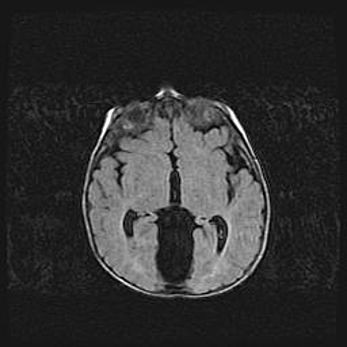

Наружная гидроцефалия с возможной атрофией височных областей.

Возраст: 28 дней

Вес: 3670 г

Пол: мужской

Окружность головы: 38 см

Срок гестации: 40 недель

Гидроцефалия головного мозга у новорожденных – это заболевание, которое характеризуется скоплением избыточного количества спинномозговой жидкости в желудочковой системе головного мозга в результате затруднения её перемещения от места выработки к месту поглощения в кровеносную систему или вследствие нарушения абсорбции. При открытой наружной форме гидроцефалии у новорожденных расширяются и переполняются субарахноидные пространства.

При нормотензивных  формах,  которые,  как  правило,  являются  следствием  перенесенных ишемических  повреждений  паренхимы  мозга,  возможно  сочетание микроцефалии  с нормотензивной гидроцефалией. В основе данных изменений лежит атрофия больших полушарий с преимущественной  локализацией  в  лобно-височных  областях.